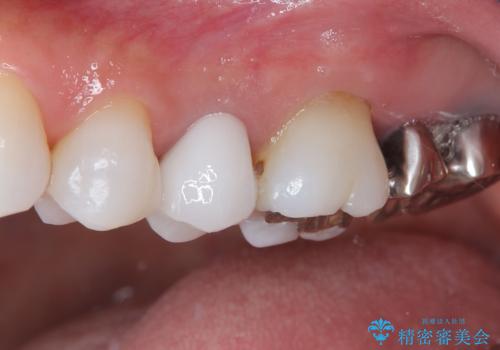

- 奥歯の銀歯とクラウンの縁から見えている歯根を気にして来院された患者様です。

歯根の見えている歯はセラミッククラウンに、詰め物の銀歯が入っている歯はセラミックインレーにて治療を行うこととしました。

笑ったときなど、口を開いたときに目立っていた銀歯や茶色い歯根が気にならなくなり、患者様には大変満足していただけました。